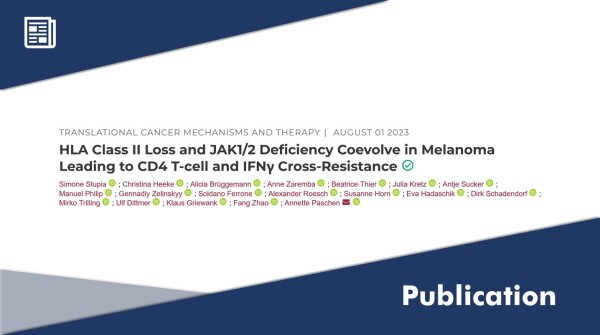

01.08.2023 - 10:37:15

A Link Between Melanoma Resistance and HLA-II Antigen Presentation

The latest paper by Annette Paschen (A13) and her group was recently published in the Journal of Clinical Cancer Research.

...

More